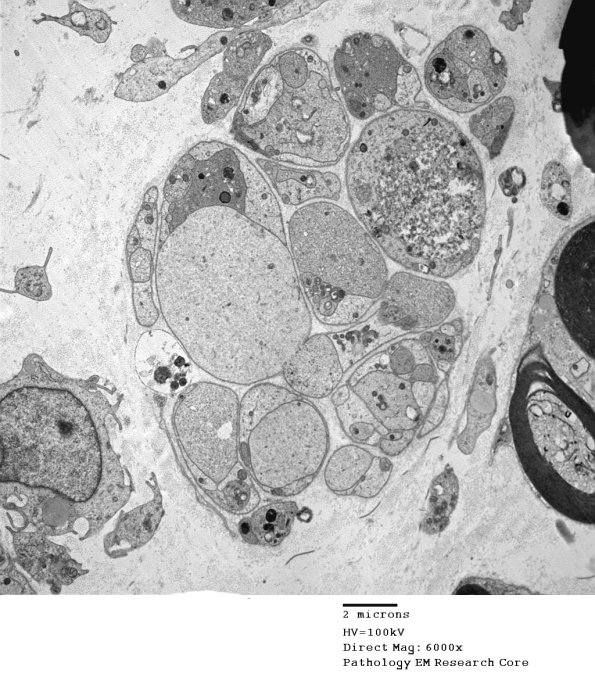

Regenerating axons differ markedly in consistency containing tubulovesicles, mitochondria and autophagosomes. Very large pale processes such as these are rarely Schwannian in origin. (electron micrograph)